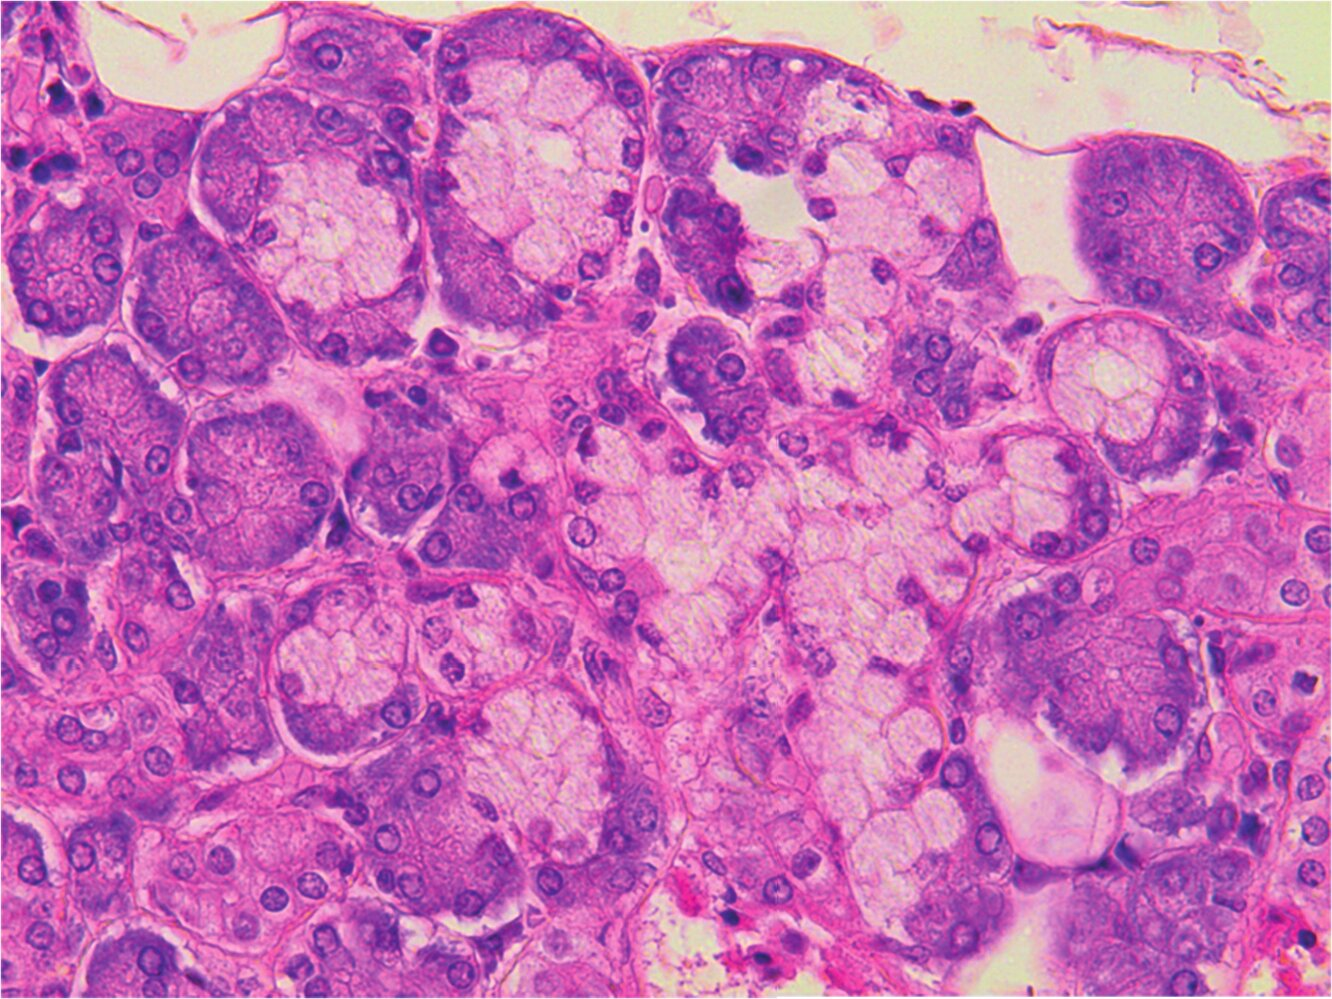

From which lymphatic organ was the histological specimen shown in the image obtained?

A. Bone marrow

B. Lymph node

C. Spleen

D. Thymus

E. Palatine tonsil (Tonsilla palatina)